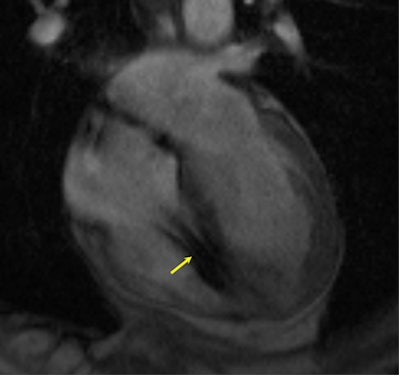

![]() |

| MR image shows a heart with a defibrillator lead in the right ventricle (yellow arrow). Image courtesy of Dr. Saman Nazarian. |